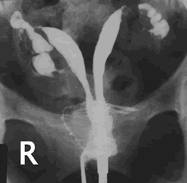

Mechanism?

Failure of paranephric ducts to completely fuse

(Bicornate uterus - note dipped-in outer contour)